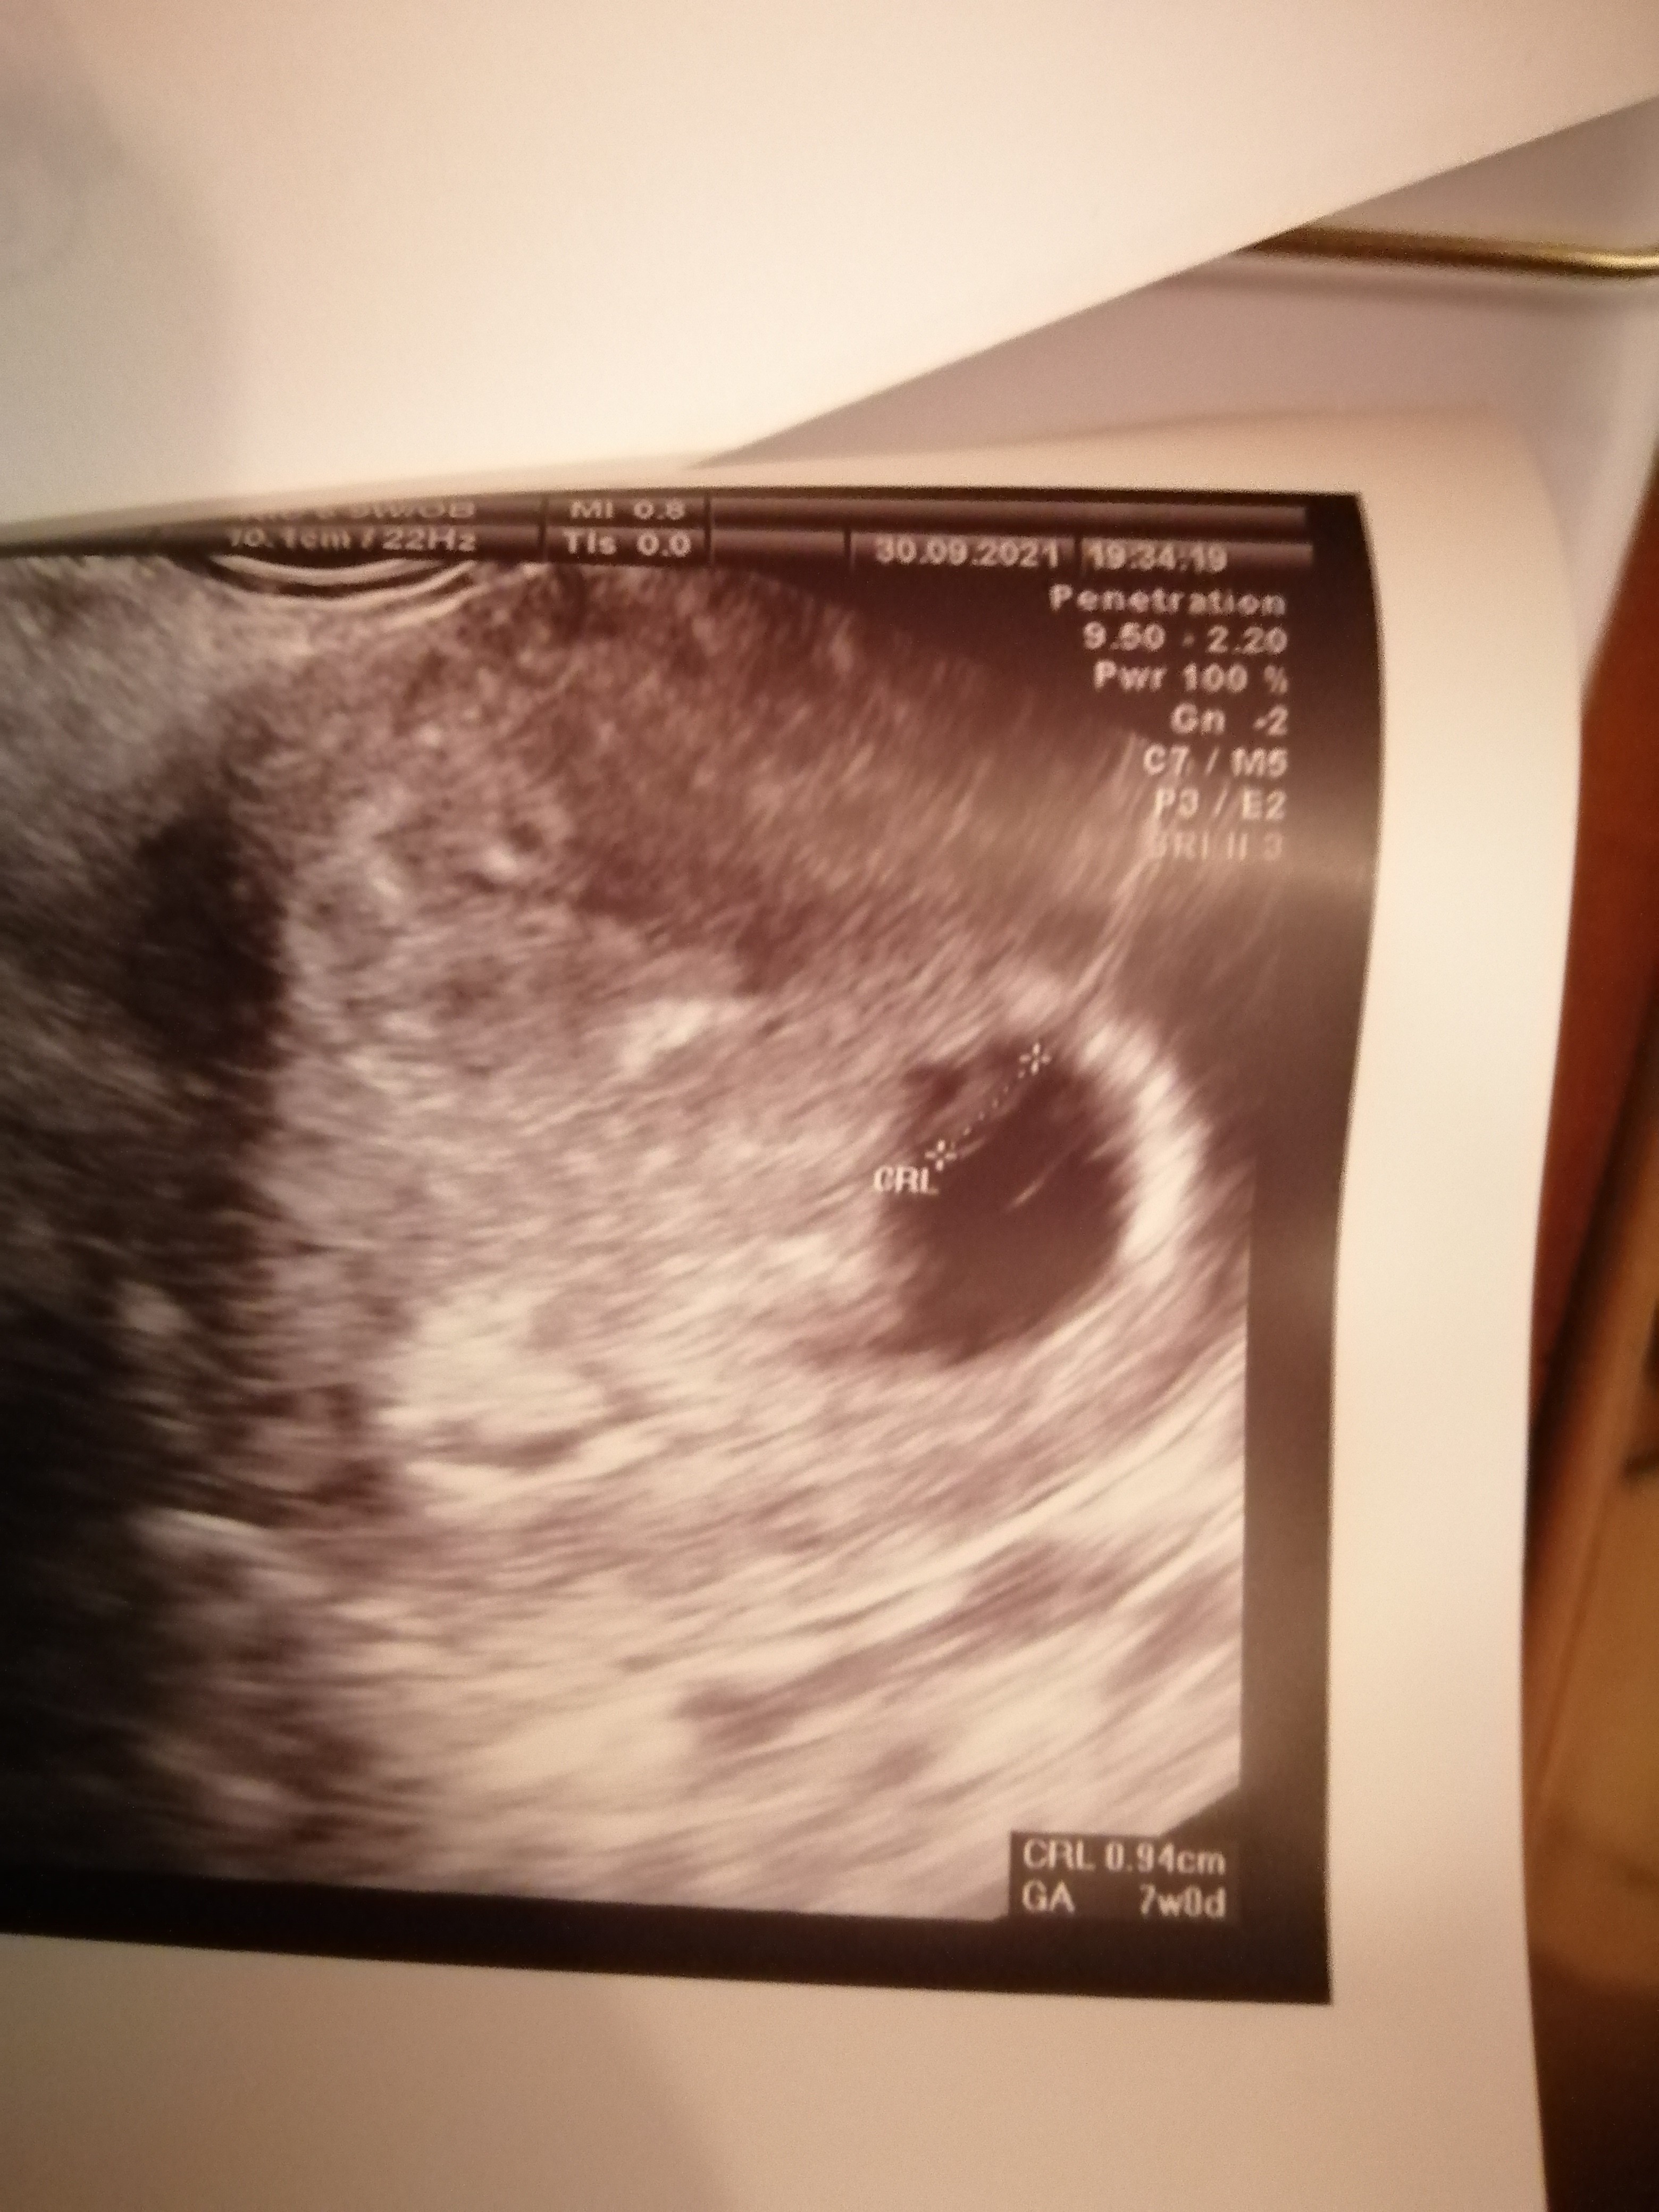

Gratki! Już całkiem duzy zarodek tez, superJest serduszko. Termin prawidłowy 19 maj.

Zobacz załącznik 1322161